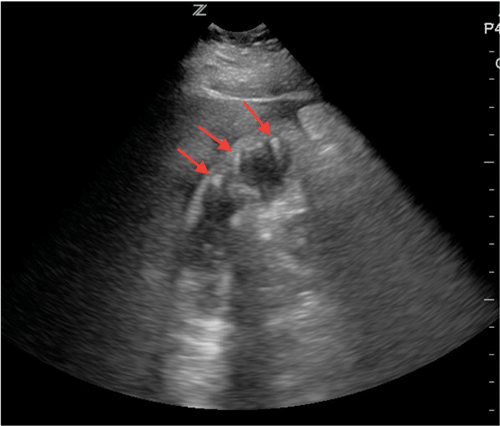

A 48-year-old female presents for right upper quadrant abdominal pain. She appears well, without jaundice, but has a fever and a positive Murphy's sign. A bedside ultrasound is completed as shown (Image 5).

The patient is diagnosed with emphysemtaous cholecystitis and subsequently undergoes an uncomplicated cholecystectomy.